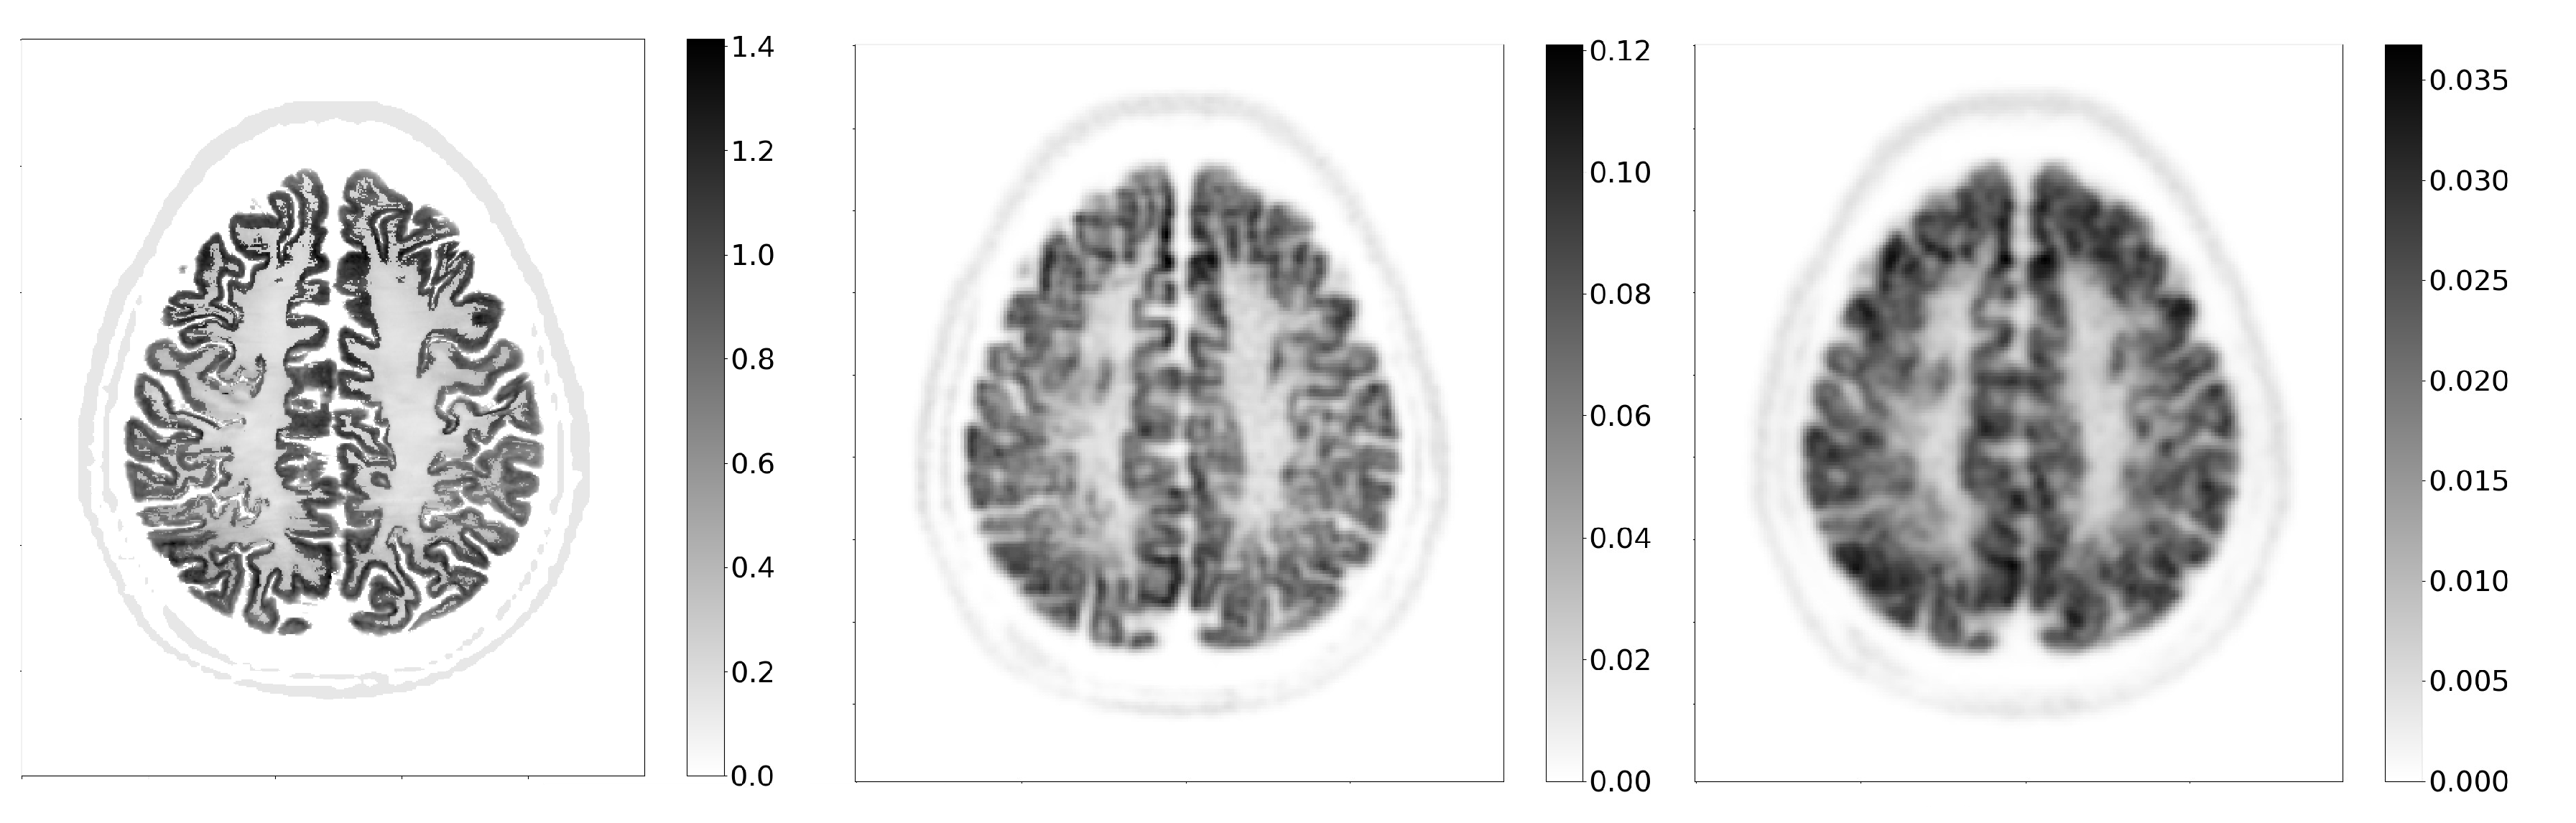

A slice of the activity phantom in the transverse plane and the corresponding reconstructed images for the CS3_L10_CTR75 and the reference scanner are shown in Figure 8.

Despite the fact that the scanner is not specifically optimised for brain imaging—for example, the crystal cross-section is large for this application—brain images are well reconstructed, with many features visible. Similarly, the reference scanner is also not optimised for brain imaging and is also mostly not used as such in clinical practice, making the comparison somewhat unfair. However, the purpose of including it was to compare the performance of the scanners on an anatomical phantom with a high degree of detail.

The structural similarity index between the slice of the activity phantom and the corresponding image reconstructed by the CS3_L10_CTR75 scanner is 0.57. In comparison, with the reference scanner and the same acquisition time, the result is 0.51. The results obtained with varying Gaussian filters are shown in Figure 9, which indicates the convergence of the index for different systems as the filter width exceeds 5 mm. At lower filter widths, the crystal-level readout scanner performs better than the submodule level, as the spatial resolution is better, despite the worse sensitivity.

Figure 8. Images of the brain phantom in the transverse plane. On the left is the activity phantom, in the middle is the image reconstructed with the CS3_L10_CTR75 scanner and on the right is the image reconstructed with the reference scanner.